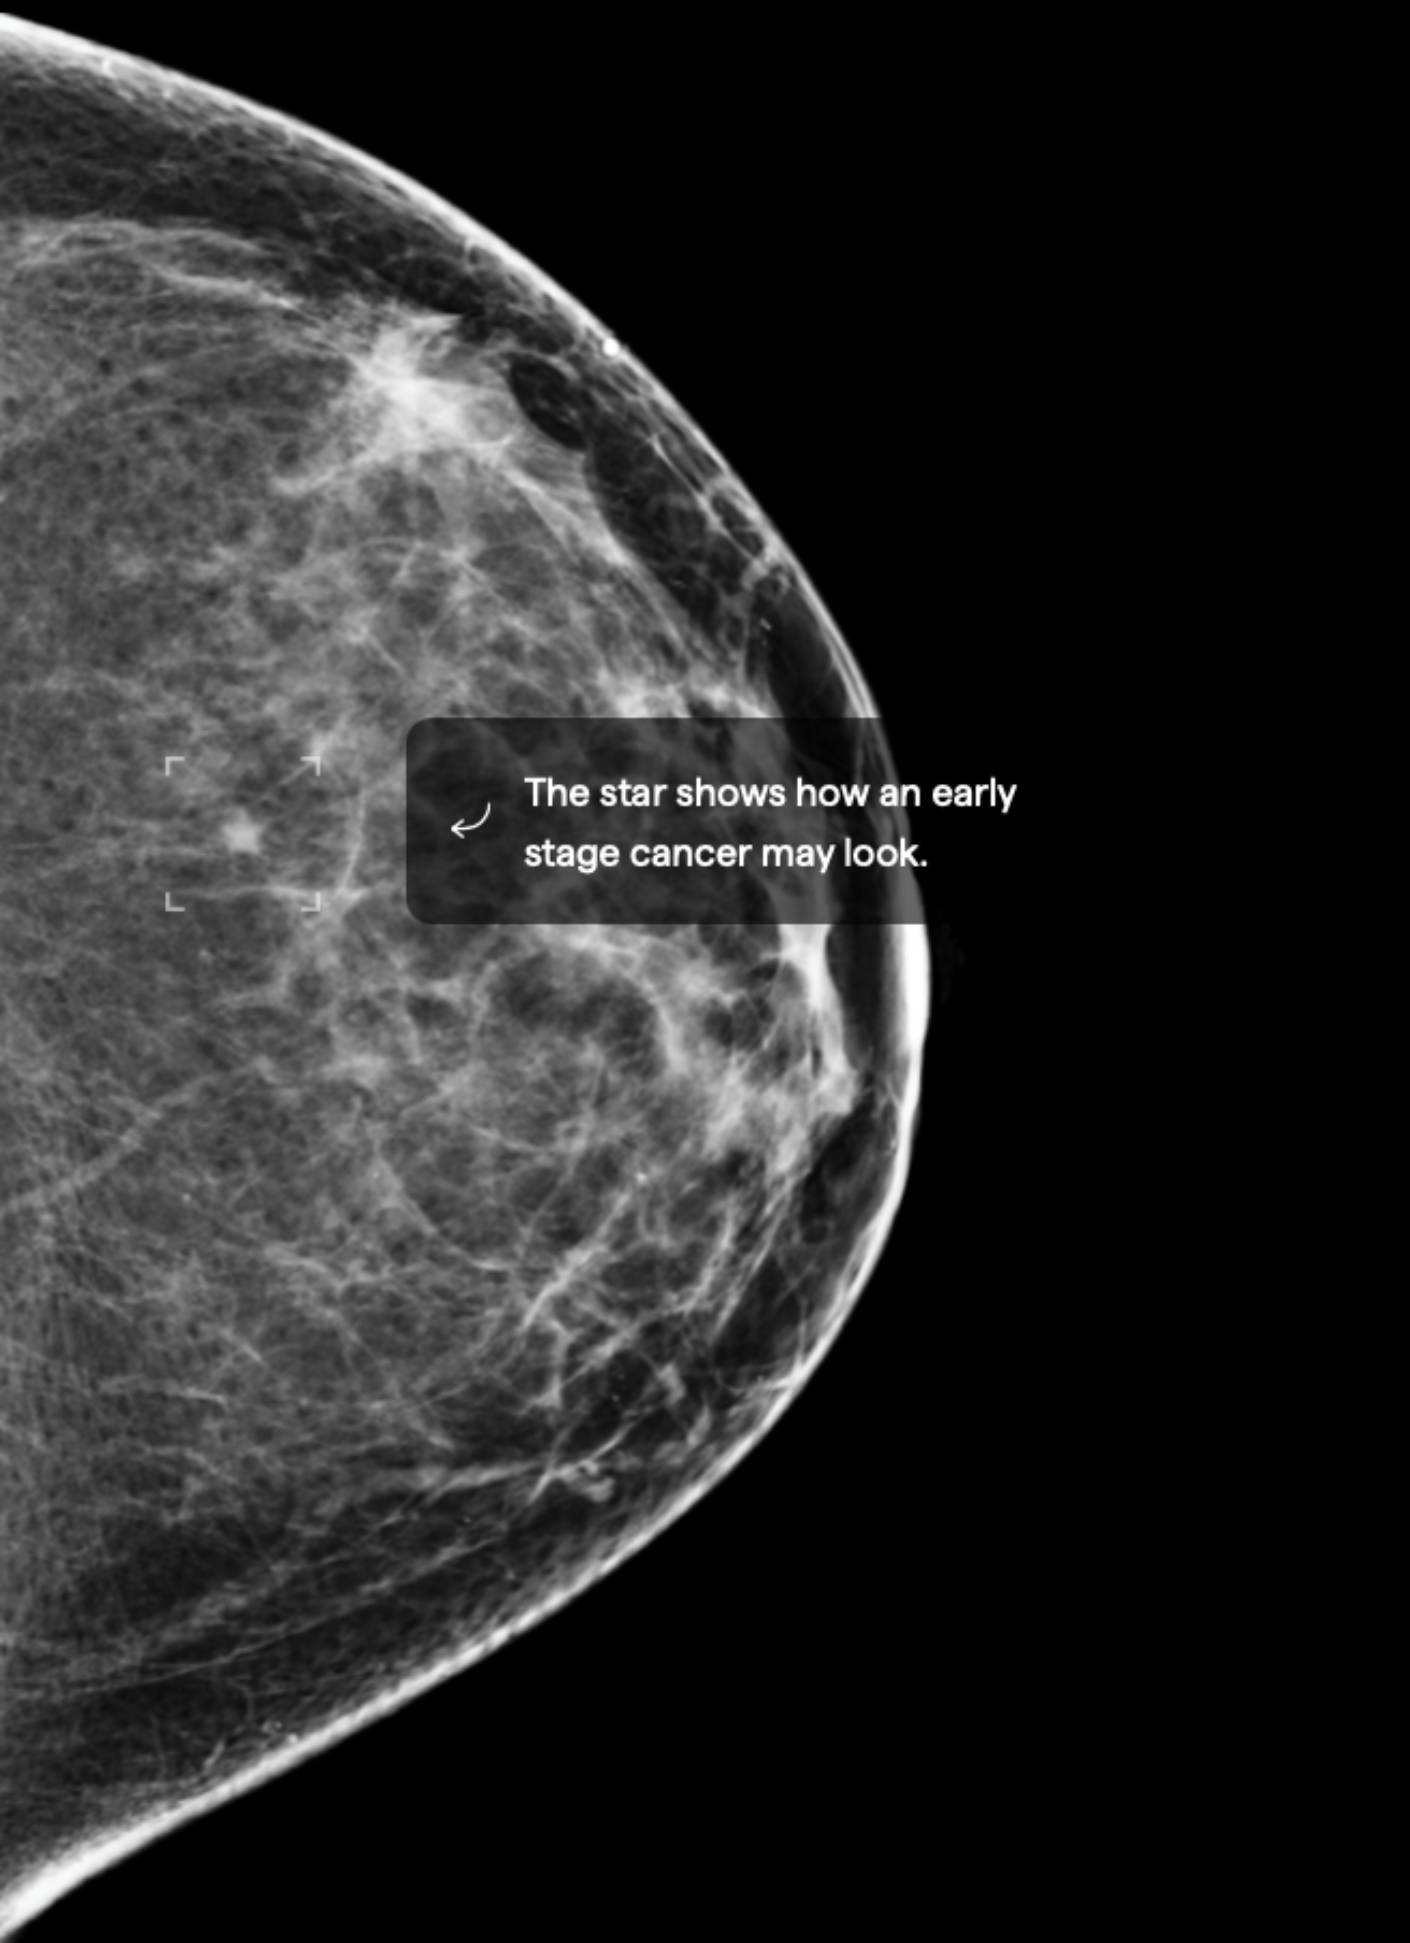

7.5% Mammographic Density

About 40% of female breasts fit category “C”. They are referred to as “heterogeneously dense breasts”.1

Your dense tissue could hide masses on your mammogram.3 Consider asking your doctor if additional ultrasound or MRI imaging should become part of your screening schedule. Also consider asking about a risk assessment to help both of you better understand your lifetime risk for breast cancer.